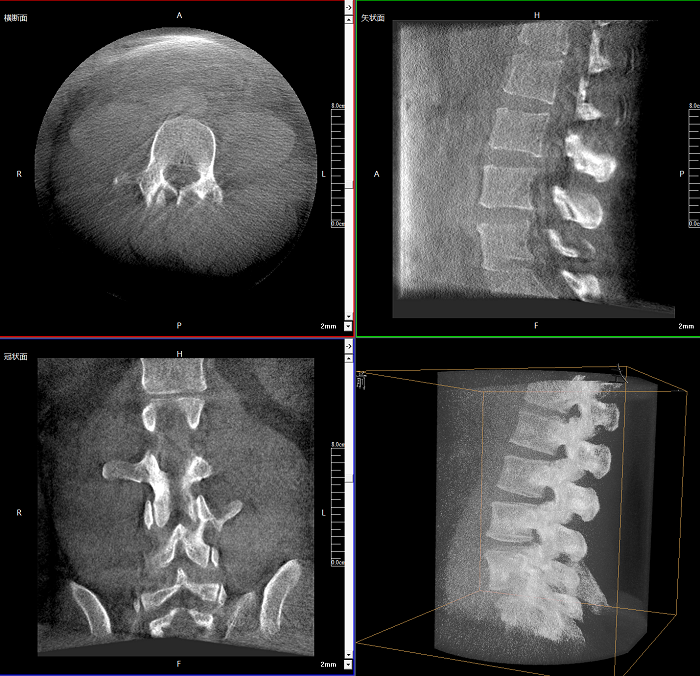

該設(shè)備可進(jìn)行快速的術(shù)中三維掃描,生成類(lèi)CT斷層圖像和立體3D圖像,保障植入物置入效果。廣泛適用于骨科、脊柱外科、矯形外科、創(chuàng)傷骨科等其他領(lǐng)域。

●極速成像僅需8秒,從數(shù)據(jù)采集結(jié)束到完成三維重建斷層影像